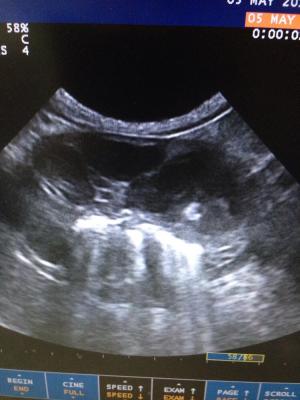

US findings: small pools of free fluid, not possible to sample. Gastric wall thickened, with mixed echogenicity, loss of detail, muscularis and serosa is intact in certain areas. Pyloric appears more normal and lesions seem to extend from fundus to Antrum. Regional LNs are enlarged and some of them very much abnormal in size shape and echostructure. Liver appears diffusely hyperexhoic with 3 focal hypoechoic areas, portal and hepatic veins dilation, GB dissension with abundant sludge and pancreatic region practically unrecognizable; I could not really visualize pancreas. Both adrenals are normal. Kidneys both in close contact with abnormal liver and Ln in right and left quadrants respectively and cranial poles Cortexes appear irregular in echogenicity. Intestines appear to have a good motility and no abnormal layering seen. Oleo exam junction not visualized…

Any ideas? It looks very much like neoplasia to me… So I did FNA but owner didn’t want to sedate and dog only allowed 2 needles. Gastric thickened mucosa is what I got, by the time I wanted to access LNs dog wouldn’t cooperate anymore. My question is… Next time, do I still try and get aspirate from gastric mucosa? Or try some other tissue? I would have chosen LNs first but I didn’t manage to get them superficially accessible after this picture was taken.